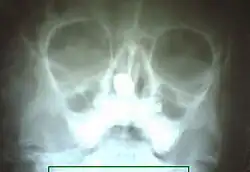

| X-ray of paranasal sinuses showing rhinolith | |